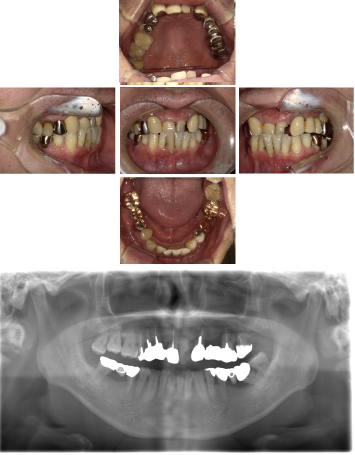

50代 インプラント治療(右上3左上3のみGBR)

| 年代・性別 | 50代・男性 |

|---|---|

| 主訴 | 入れ歯が合わず毎日ヨーグルトしか食べることができないので、しっかり咬めるインプラントにしたい。 |

| 部位 | 右下⑦⑥5④ 上顎③2①①2③ 左下67 |

| 治療期間 | 約9ヶ月 |

| 費用 | ¥4,273,500(税込) |

| 副作用・リスク |

|